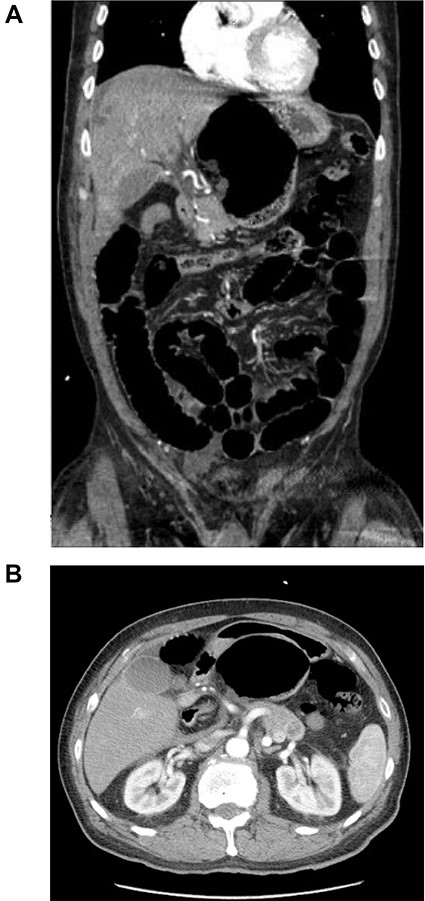

A 67-year-old male with a past medical history of prostate cancer, hypertension and prior open right inguinal hernia repair presented to the emergency department (ED) with sudden onset nausea, vomiting and abdominal pain for 2 h. The abdomen was non-distended and slightly tender in the epigastrium. A clinical diagnosis of pancreatitis was made based on physical examination, history and a mildly elevated lipase and the patient was discharged home with antiemetic medications by the ED providers. The patient presented back to the ED 2 days later with worsening abdominal pain, nausea, vomiting and obstipation. At this time his abdomen was distended and tender to palpation in the epigastrium without peritoneal irritation. Due to his obstructive clinical picture, a CT scan of the abdomen and pelvis with IV contrast (Fig. 1) was obtained in the ED. The scan was read as a possible volvulus versus an internal hernia causing small bowel obstruction. A nasogastric tube was placed after he was admitted to the surgical unit with partial resolution of his abdominal tenderness and distention. A barium enema (Fig. 2) was performed to rule out an obstructing distal mass, which showed a transition point at the hepatic flexure.

CT scan of the abdomen and pelvis with IV contrast. (A) Coronal view shows internal herniation of the cecum through the foramen of Winslow. (B) Axial view demonstrates the same findings with the stomach displaced both laterally and anteriorly by the cecum. Of note there was 1.5-cm ring-enhancing lesion located in the body of the pancreas found incidentally.